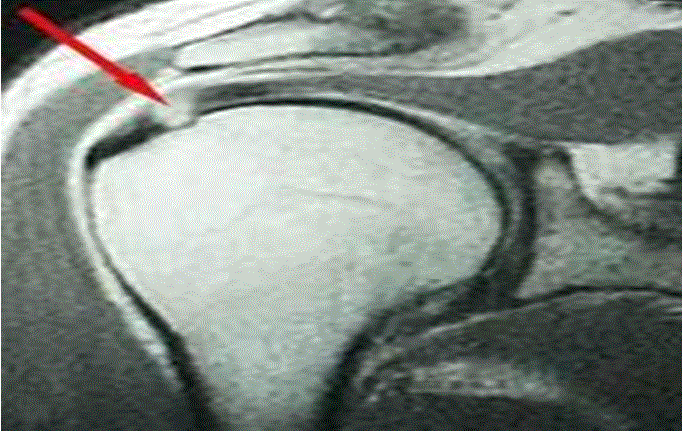

Όσον αφορά την διάγνωση ο υπέρηχος όσο και η μαγνητική τομογραφία του ώμου είναι εδώ η απεικονιστική εξέταση επιλογής. Σε αυτήν βλέπουμε με μεγάλη ακρίβεια όλη την ανατομία του ώμου και ιδίως την ύπαρξη ρήξεων στο πέταλο στροφέων.

Σε περίπτωση έντονων συμπτωμάτων, ο ασθενής κατά πάσα πιθανότητα θα ζητήσει άμεσα ιατρική συμβουλή. Το παράξενο όμως, ειδικά σε αυτές τις υπακρωμιακές φλεγμονές, είναι ότι συχνά τα συμπτώματα είναι από πολύ ήπια έως και ανύπαρκτα. Μπορεί επομένως να υπάρξουν επανειλημμένες φλεγμονές χωρίς ο ασθενής να έχει αντιληφθεί τίποτα. Μετά από μεγάλο χρονικό διάστημα επαναλαμβανόμενης τριβής στο σημείο αυτό, μπορεί να δημιουργηθεί μια ρήξη στο πέταλο των στροφέων (rotator cuff tear). Η ρήξη αυτή, στην πλειονότητα των περιπτώσεων, βρίσκεται στον υπερακάνθιο μυ καθώς αυτός βρίσκεται στο κλασσικό σημείο πρόσκρουσης. Αυτό τυχαίνει να είναι και το σημείο στο οποίο ο υπερακάνθιος από μυς γίνεται τένοντας και η αιμάτωσή του μειώνεται αισθητά. Τέτοιες εκφυλιστικές ρήξεις του υπερακανθίου μπορεί να υπάρχουν για χρόνια προτού ο ασθενής αντιληφθεί ότι κάτι δεν πάει καλά με τον ώμο.